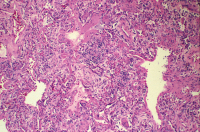

DAD - EVALI

Abbildung 3: Organisierende Pneumonie nach DAD – der Patient hat nach einer Therapie auf einer Intensivstation überlebt (H & E, X 200).

Keywords: DADEVALIHistologisches Präparat